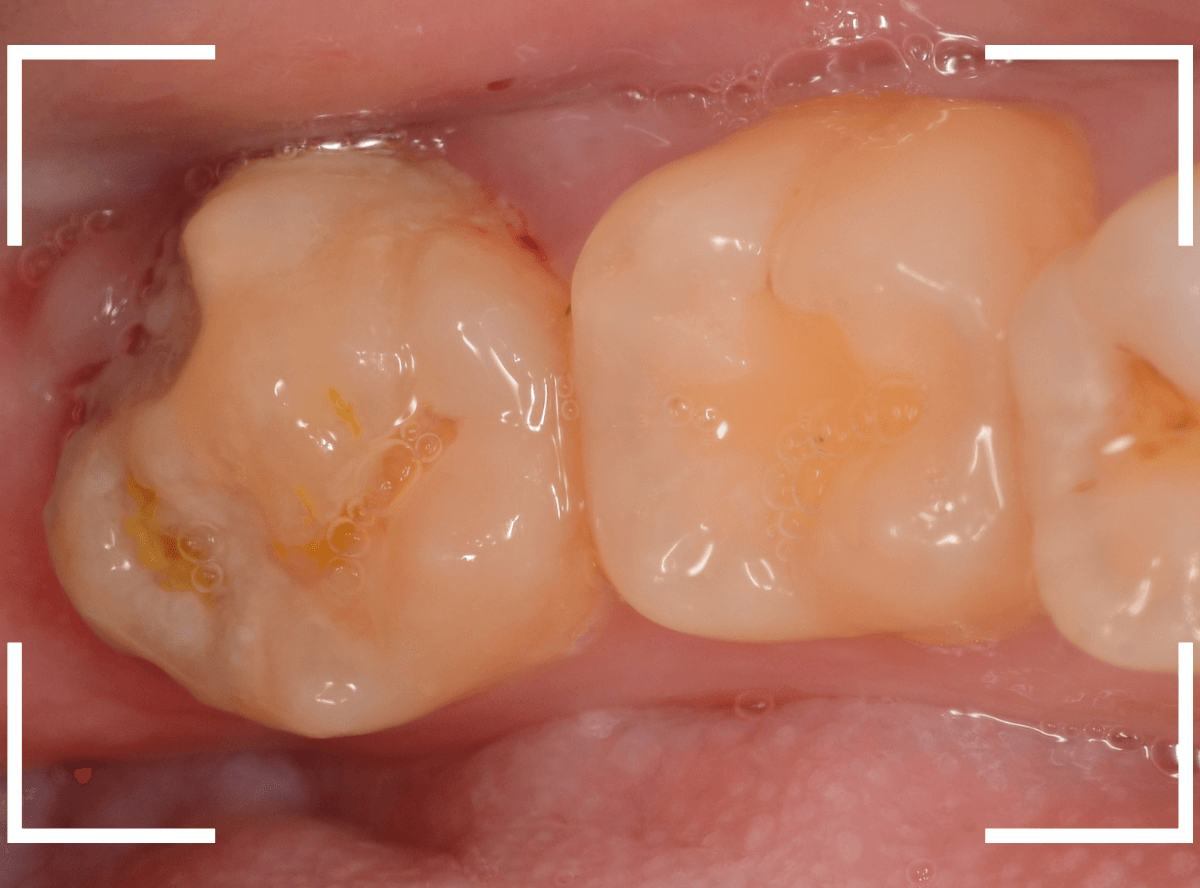

ここでは、比較的簡単なおやしらずの抜歯の例を中心にご紹介します。

このようなおやしらず、あなたはありませんか?